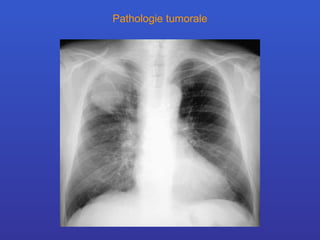

Pathologie tumorale